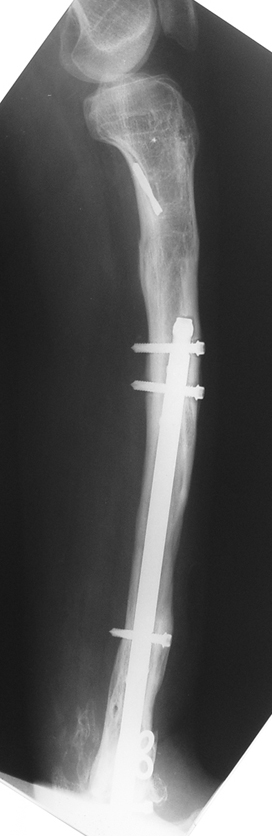

Bu Bacak Kısalık tipi bir kırığın kısalmış pozisyonda kaynaması ile oluşur. Bir çok vaka yetişkinlerde görülür ve sadece bir uzatma ile tedavi edilebilir. Ek deformiteler de aynı anda düzeltilebilir. Bu hastaların çoğu çivi üzerinden uzatma veya tam implante edilen çivi ile tedavi edilebilirler.